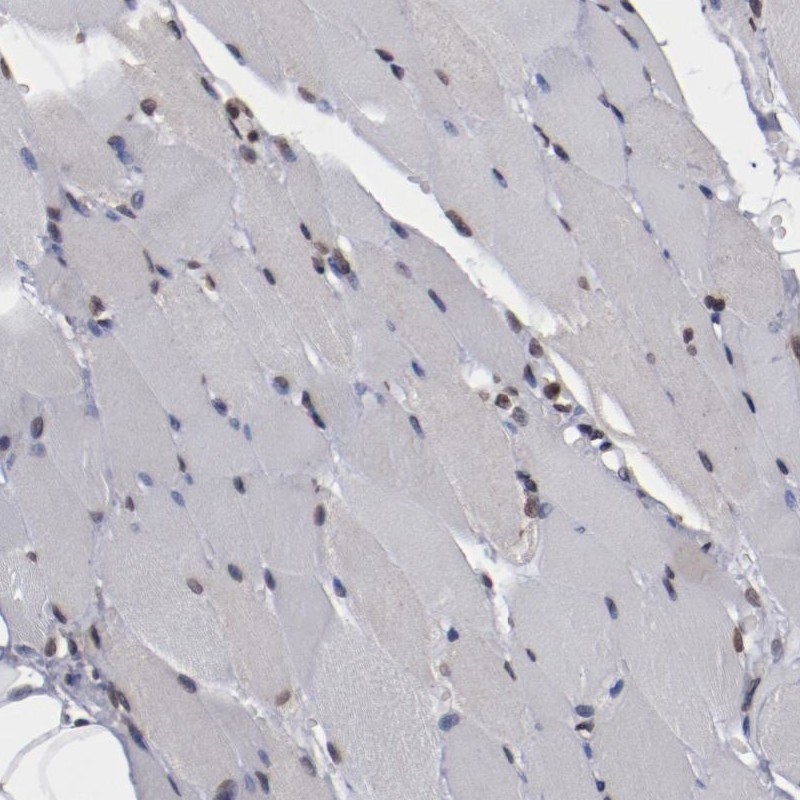

Immunohistochemistry analysis in human seminal vesicle and skeletal muscle tissues using Anti-AKT1 antibody. Corresponding AKT1 RNA-seq data are presented for the same tissues.